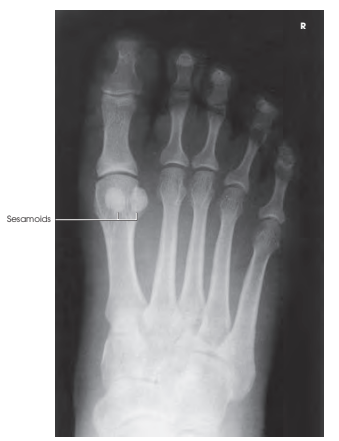

Structures shown (보여지는 구조들)

- AP 투사 결과:

발의 전면을 보여주며, 발바닥(dorsum)에서부터 지골(phalanges), 중족골(metatarsals), 및 족근골(tarsals)까지 포함됩니다.

- 사용 용도:

- 뼈 골절의 위치 확인

- 관절염, 외상 또는 일반적인 발 스캔 검사용

Evaluation Criteria (평가 기준)

- 다음 사항이 명확히 보여야 합니다:

- 발 전체의 해부학적 구조:

- 발가락에서 족근골까지 포함

- 중족골 사이의 간격이 균일하게 유지됨

- 발의 회전 없음:

- 두 번째에서 네 번째 중족골 사이의 간격 유지

- 관절 공간의 선명도:

- **IP(MTP 및 TMT 관절)**의 공간이 열려 있어야 함

- 연부 조직과 뼈 조직 세부 사항들이 선명해야 함